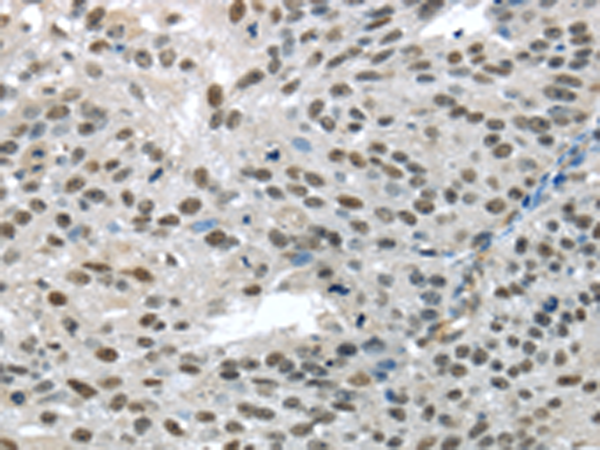

分类: 科研抗体货号: P08902别名: EG1; magicin; 1500003D12Rik应用: WB,IHC反应种属: Human, Mouse, Rat